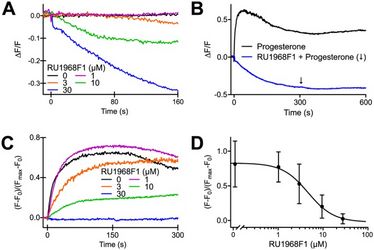

20.09.2018

Anzahl Aufrufe: 14913

New article published in "The Journal of Neuroscience" (Volume 38, Issue 38)

New article published in "The Journal of Neuroscience" (Volume 38, Issue 38)